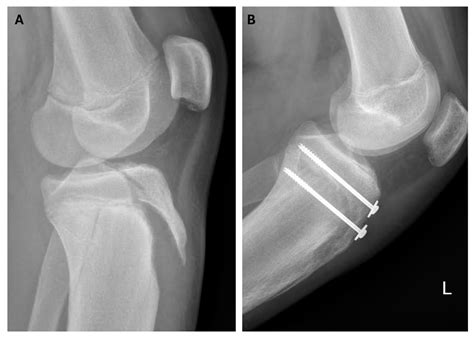

To confirm the diagnosis, medical professionals typically utilize imaging studies. X-rays are the gold standard for visualizing the displaced bone fragment and determining the severity of the fracture. In more complex or comminuted cases, an MRI may be ordered to assess the condition of the surrounding soft tissues, including the patellar tendon and menisci.

Treatment for a Tibial Tuberosity Avulsion depends heavily on the displacement of the bone fragment. For minor fractures where the bone has not moved significantly, immobilization in a long leg cast or brace for several weeks may be sufficient. During this time, the goal is to allow the bone to heal in its natural position.

However, if the fragment is displaced or if the knee joint is compromised, surgical intervention is mandatory. The surgical procedure typically involves:

• Open Reduction Internal Fixation (ORIF): The surgeon makes an incision to visualize the bone fragment.

• Hardware Placement: The loose piece of bone is secured back to the main tibia using screws, wires, or specialized anchors.

• tibial tuberosity fracture radiology